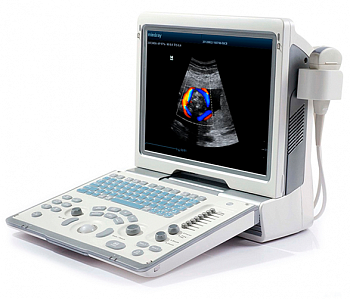

Клинические изображения

Область исследования

- Абдоминальные исследования

- Акушерство

- Гинекология

- Кардиология

- Неврология

- Травматология

- Ортопедия

- Урология

- Эндокринология

- Ангиология

- Педиатрия

- Неонатология

- Транскраниальные исследования

- Онкология